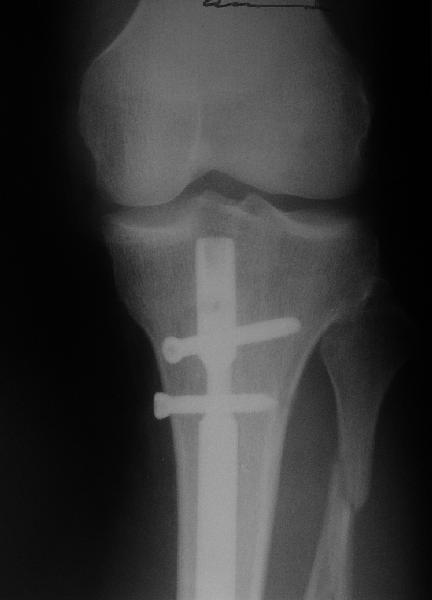

Добрый день, уважаемые коллеги. На консультацию обратился мужчина 30

лет. Месяц назад по месту жительства ему был выполнен закрытый

интрамедуллярный остеосинтез большеберцовой кости по поводу

спирального перелома обеих костей голени. Ходит с ограниченной

нагрузкой на ногу. Направлен из травмпункта по поводу оставшегося

смещения отломков. У нас разделилось мнение коллег по вопросу  - есть

ли необходимость в закрытом интрамедуллярном реостеосинтезе с

исправлением оси или только ограничиться динамизацией гвоздя.